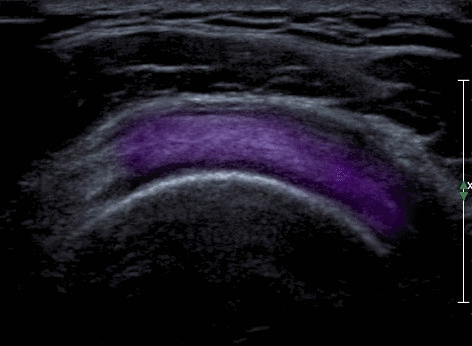

Hình 2: Hình ảnh siêu âm khảo sát gân cơ trên gai[5].